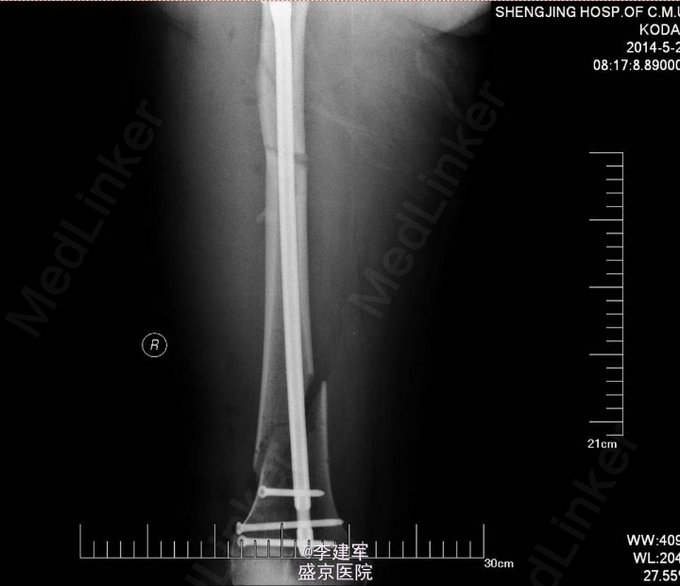

诊断:右股骨干粉碎性骨折 患者右股骨干粉碎性骨折,拟行右股骨干骨折闭合复位内固定术。

长骨的干的骨折,行髓内针闭合复位,有助于患者早期下地行走,且创口小。粉碎性骨折不破坏骨膜,骨的血运未破坏。扩髓相当于髓内植骨,有利于生长。所以本次手术行髓内针闭合复位。